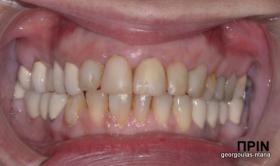

ΟΛΙΚΗ ΑΠΟΚΑΤΑΣΤΑΣΗ ΑΝΩ ΓΝΑΘΟΥ

Η ασθενής ήταν δυσαρεστημένη από την εμφάνιση των άνω δοντιών της. Ήθελε τα δόντια της να αποκτήσουν ομοιόμορφο, πιο λευκό χρώμα κ να αποκτήσει ένα πιο αρμονικό χαμόγελο με φυσική εμφάνιση. Λόγω των εκτεταμένων εμφράξεων σύνθετης ρητίνης στα πρόσθια δόντια, των εμφράξεων αμαλγάματος στα πίσω αριστερά δόντια αλλά και της υπάρχουσας γέφυρας στα πίσω δεξιά δόντια, και σε συνδυασμό με την επιθυμία της ασθενούς για φυσικό αποτέλεσμα αποφασίστηκε η τοποθέτηση ολοκεραμικών στεφανών στα δόντια της άνω γνάθου. Στη θέση του δεύτερου προγομφίου δεξιά τοποθετήθηκε εμφύτευμα. Πραγματοποιήθηκε περιοδοντική θεραπεία, ενδοδοντικές θεραπείες (απονευρώσεις) κ τοποθετήθηκαν ενδορριζικοί άξονες υαλονημάτων όπου κρίθηκε απαραίτητο. Σε όλη τη διάρκεια της θεραπείας η ασθενής ήταν καλυμμένη αισθητικά κ λειτουργικά με προσωρινές αποκαταστάσεις.